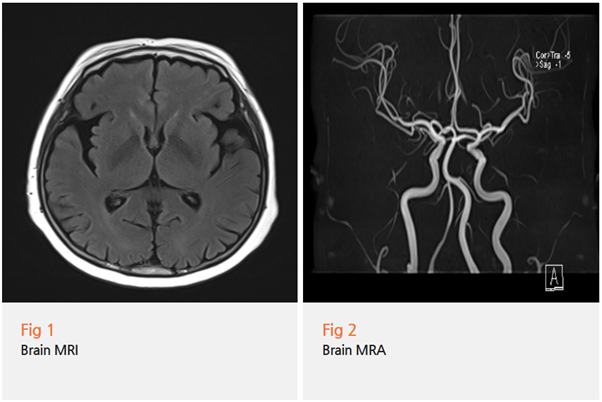

1️⃣ 먼저 뇌 MRI와 MRA를 시행해서

뇌경색이나 다른 뇌질환 가능성을 배제했어요

결국 뇌 MRI에서 다른 뇌질환은 발견되지 않았고,

임상 양상상 파킨슨병으로 진단을 내릴 수 있었습니다.